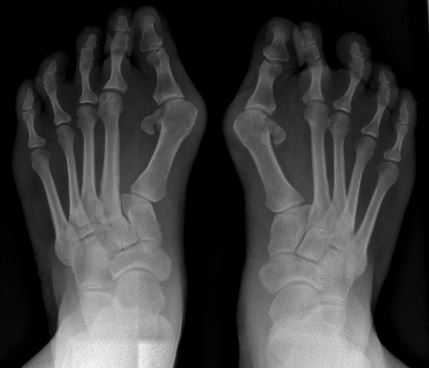

무지외반증이란 엄지발가락의 중족지관절이 튀어나와 중앙쪽으로 굽어져 발의 형태가 변형된 것을 말합니다. 엄지발가락이 두번째 발가락쪽으로 심하게 휘고, 엄지발가락과 관절을 이루는 종족골은 반대로 안쪽으로 치우쳐서 변형이 일어난 것인데요.

무지외반증은 보기에도 나쁠뿐만 아니라 신발을 신었을때 돌출된 뼈와의 마찰을 통해 심한 통증이 유발됩니다. 또한 엄지발가락쪽에 실려야할 압력이 두번째, 세번째 발가락쪽으로 이동되면서 발바닥쪽에 굳은 살이 생길 수 있습니다.

통증이 심해서 병원을 방문했다면, 전문의가 육안으로 또는 엑스레이를 통해서 무지외반증을 진단할 수 있습니다. 무지외반증이 진행성 질환인가에 대해서는 아직 논란의 여지가 있으며, 자연치료 가능성에 대해서는 알려진 바가 없습니다. 따라서 수술적인 치료와 보존적인 치료가 병행되어야만 치료될 수 있다고 보여지는데요.